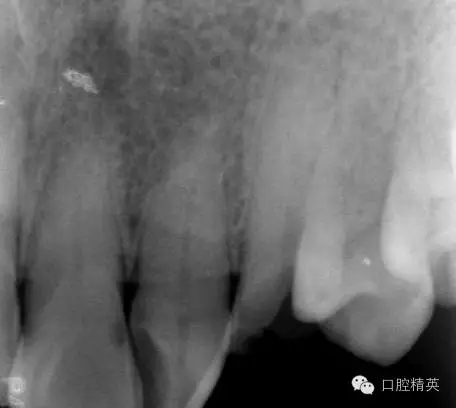

圖2 治療前X片: 23殘根,根尖區(qū)骨密度降低.

圖3 根管治療后X片